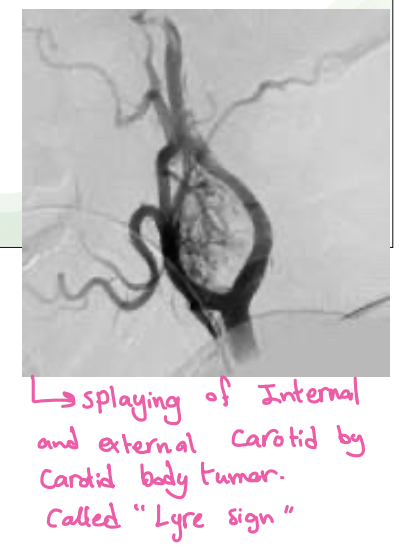

Arteriography-Shows the carotid bifurcation to be splayed open by the mass which is rich in vascularity

What is Lyre sign in CT scan? angiogram - most likely carotid body tumour